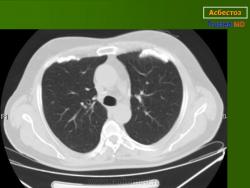

При развитии асбестоза на рентгенограмме можно увидеть неправильной формы или линейные очаговые тени. В начале такие изменения появляются в нижней трети легкого(их), когда заболевание начинает прогрессировать, то изменения определяются в верхней и средней третях. Если фиброз сильно выражен, то граница сердечной тени становится нечеткой или же возникают однородные ограниченные затемнения легочных полей. Нарастание фиброза влечет за собой формирование сотового легкого, имеющего классическую рентгенологическую картину, т. е. величины смешаны с мелкими полостями (их диаметр составляет, как правило, от 7 до 10 мм), видны очаговые тени разной формы, и облитерация целых ацинусов.

Рентгенологические признаки асбестоза I стадии: нерезкое усиление легочного рисунка за счет перибронхиального, пери-васкулярного и межуточного фиброза преимущественно в прикорневых и средних поясах легких, имеющего сетчатую и мелкопетлистую структуру, небольшие изменения плевры (утолщение, базальные спайки); корни легких несколько деформированы, уплотнены.

На рентгенограммах сосудисто-бронхиальный рисунок резко усилен, имеет более грубую сетчатую структуру. Иногда обнаруживаются немногочисленные мелкопятнистые тени узелкового характера. Прозрачность легочных полей повышена. Корни легких значительно уплотнены, расширены. Могут выявляться начальные признаки легочного сердца.